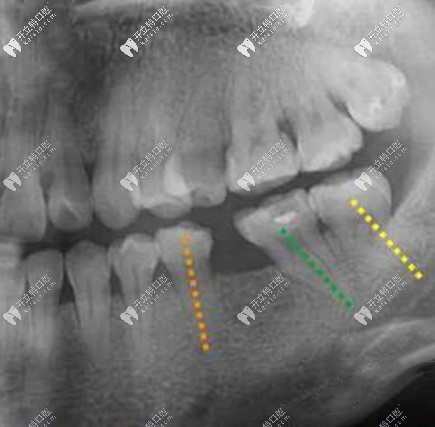

我選的是美加瓷貼面,我的上牙有幾顆牙牙齦萎縮,需要做牙齦瓷美學(xué)修復(fù),補(bǔ)償前牙美學(xué)區(qū)牙齦缺失的部分。

我想做玻璃陶瓷,但是醫(yī)生說玻璃陶瓷因?yàn)橥ㄍ感蕴?,有點(diǎn)遮不住我本身的牙色,像我這種四環(huán)素牙顏色較深的建議選鑄瓷材料,材料稍厚些,通透性沒有玻璃陶瓷好但是遮色效果好。上下一共做了十六顆,費(fèi)用是按顆收費(fèi),瓷貼面粘接技術(shù)不過關(guān)很容易崩瓷和脫落,做的好的話沒毛病是不用取的,也就是說如果保護(hù)好可以用很久。